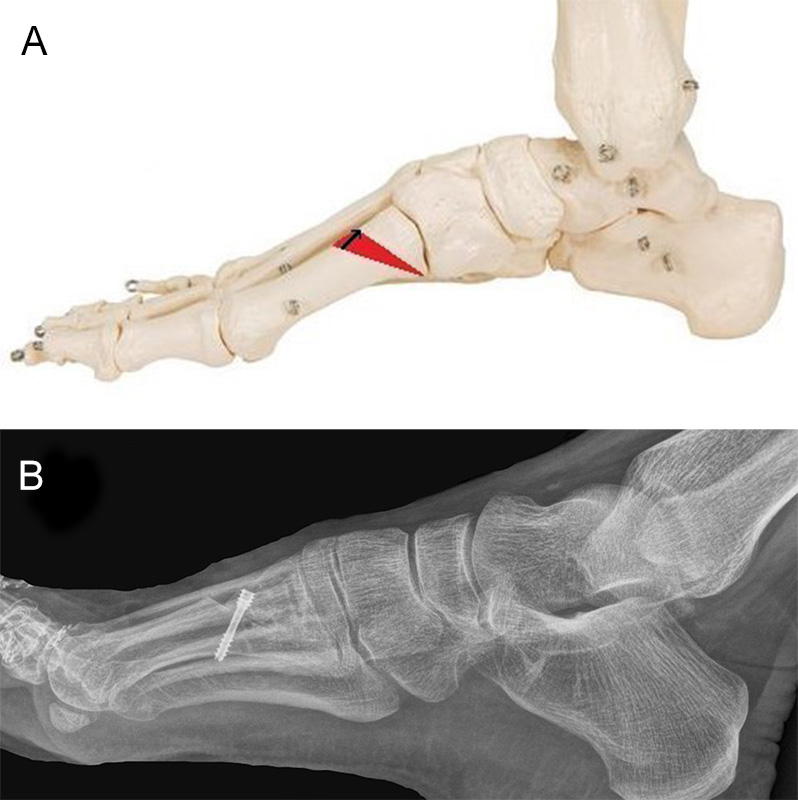

Um die Steilstellung des ersten Os metatarsale und die damit verbundene Entwicklung eines plantaren Ulkus unter MTK-1 zu verhindern, kann in minimalinvasiver Technik durch eine schräg verlaufende, dorsalbasige Keilosteotomie im proximalen Anteil des Os metatarsale I das Metatarsaleköpfchen angehoben werden. Diese Maßnahme führt zu einer Druckreduktion und in der Regel zu einer Abheilung des Ulkus. Die Osteotomie wurde 1998 erstmalig in der offenen Technik beschrieben, wird aber inzwischen auch in minimalinvasiver Technik durchgeführt 25. Über einen dorsomedialen Hautschnitt wird am ersten Strahl ein dorsalbasiger, nach distal geöffneter Keil reseziert (Abb. 11). Der Eintrittspunkt der Fräse befindet sich knapp distal des Tarsometatarsale-I-Gelenks. Die plantare Kortikalis des Os metatarsale I wird dabei erhalten. Die Breite des dorsalen Keils bestimmt das Ausmaß der Korrektur und kann durch Verwendung einer entsprechenden Fräse modifiziert werden. Durch einen Keil mit einer Basis von 3,4 mm lässt sich das Os metatarsale I um ca. 5° anheben. Hat der dorsale Keil eine Basis von 6,7 mm, wird die Achse des Os metatarsale I um 10° nach dorsal korrigiert (Abb. 12). Wird eine Korrektur von ca. 5° angestrebt, bietet sich an, eine Fräse mit einem Durchmesser von 2 mm zu verwenden. Der Substanzverlust bei einem Schnitt liegt bei 2-2,5 mm. Für eine weitere Knochenresektion wird die Osteotomie durch plantaren Druck auf das Os metatarsale I Köpfchen geschlossen und die Fräse nochmals durch die geschlossene Osteotomie geführt. Durch mehrmalige Wiederholung dieser Prozedur lässt sich die Korrektur sehr genau einstellen. Für eine Korrektur von 10° oder mehr kann eine Keilfräse mit entsprechend größerem Durchmesser verwendet werden. Nach Schließen der Osteotomie erfolgt die temporäre Fixation mittels eines K-Drahtes und die Osteosynthese mit einer oder zwei Zugschrauben. Die Nachbehandlung beinhaltet eine sechswöchige Ruhigstellung im Verbandsschuh unter Fersenbelastung.

Zum Lesen der Bildbeschreibung und zur Vollansicht bitte das Bild anklicken.

Abbildung 11

Tabelle 1: In der Tabelle wird der Grad der Korrektur in Abhängigkeit des entfernten dorsalen Keils bei einer schräg verlaufenden Keilosteotomie des Os metatarsale 1 angegeben 26.

Grad der gewünschten Dorsalextension

Benötigte Länge des dorsalbasigen Keils

5°

3,4 mm

10°

6,7 mm

15°

11,0 mm

20°

14,5 mm

25°

19,0 mm

Abbildung 12